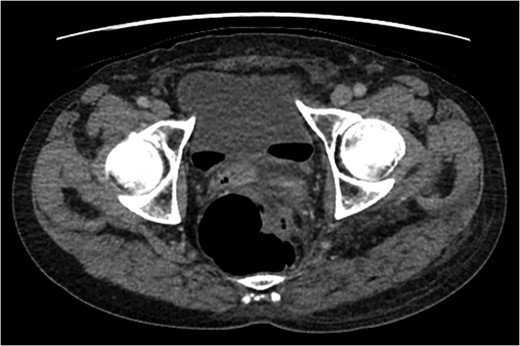

A rare complication of diverticular disease is the formation of fistulas, most commonly either colo-vesical or colo-vaginal. We present the unusual case of a perforated sigmoid diverticulum forming a colo-gluteal fistula and presenting initially as a gluteal abscess in an otherwise asymptomatic patient. After drainage of the gluteal abscess, the patient re-presented with faecal loss from the abscess drainage site. Imaging revealed fistulous communication between the sigmoid and the left obturator internus muscle, tracking to the gluteus maximus with associated abscess and cutaneous communication to the site of previous drainage. The patient underwent an emergency Hartmann's procedure with lay open/abscess drainage of the gluteal cavity. Post-operatively the patient experienced continuing discharge from the gluteal fistula despite repeated drainage and debridement causing considerable morbidity, inconvenience and misery. Clinicians should maintain a high index of suspicion when presented with a gluteal abscess and should consider the possibility of an intra-abdominal source.

An emergency Hartmann's procedure was performed under general anaesthetic through a lower midline incision as well as lay open of the perineal fistula. On opening the abdomen, a perforated diverticulum was identified extending into the left lateral pelvic wall. A standard Hartmann's procedure was performed, with sigmoid colectomy, division of rectum at recto-sigmoid junction and a tension-free stoma formed in left hypochondrium. The left buttock abscess cavity extended by a further 2–3 in. and the cavity then packed.

Following the operation, the patient had a short and uncomplicated critical care stay and was subsequently discharged. He has since continued to experience ongoing discharge from the fistula with follow-up imaging showing a reduction in the size of the abscess cavity but continuing patency of the fistula tract, despite repeated wound debridement and packing, drainage of the fistula and rectal washout.